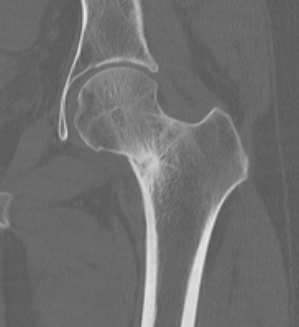

CT

Fracture line

CT demonstrating incomplete fracture at inferior neck

CT demonstrate likely complete fracture, with some displacement